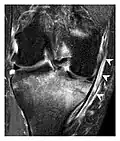

Figure 1: A 56-year-old woman presenting with left knee pain after a fall. (a) Initial anteroposterior radiograph was considered normal, however, subtle cortical disruption of the anterior rim of the medial tibial plateau, medial to the tibial spine, is noted (arrow). (b) Coronal T1-weighted MRI confirms the cortical disruption (arrow) and shows extensive fracture through the proximal tibia. (c) Coronal proton density-weighted image with fat saturation shows extensive edema in the subchondral bone. Note also hypersignal adjacent to the medial collateral ligament corresponding to a grade I sprain (arrowheads).[1]

Figure 9: Proximal metaphyseal fatigue fracture of the tibia in a 27-year-old recent male military recruit. (a) Anteroposterior radiograph is within normal limits. (b) Coronal T1-weighted MR image shows a marked linear hypoattenuation along the medial tibial metaphysis (arrow) surrounded by diffuse hypointensity in keeping with posttraumatic edema.[1]